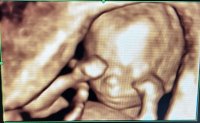

I have my private scan on Wednesday. Can’t wait!Thanks, you too! How’s everyone doing? Any upcoming scans or Apts?

My kids made a big fuss about me making a gender reveal for them. But once they knew we had our scan and had found out they couldn’t waitIn a perfect world, I was going to stay team yellow but I’ve decided since I’m on my own it will be easier to prepare for baby’s arrival if I know the gender. I’ve booked a private scan for this Tuesday.. I haven’t told my kids so I’ll probably do a gender reveal for them when I come up with an idea

I’m sure they’ll love that!We did a gender reveal with my little boy for the kids and my step daughter popped the balloon before they were supposed to. They are coming to the scan with us tomorrow.